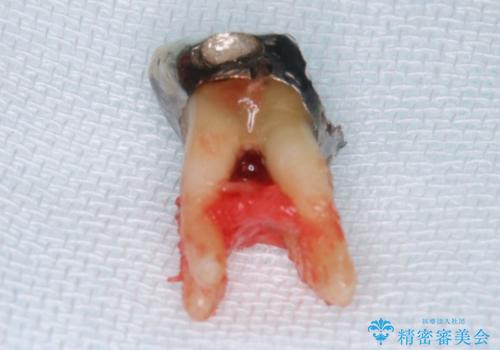

- Ⅲ度の分岐部病変をきたした第1大臼歯を抜去、待時しインプラントによる咬合回復を計画した。

奥歯の根の又の部分の歯周病(=分岐部病変)が進行してしまった場合、

ケースによりますが、いずれの場合も不安要素をかかえたまま歯を温存することになるため、それらを取り除く・かつ感染源を取り除くために歯を抜去するのも効果的な治療法といえます。